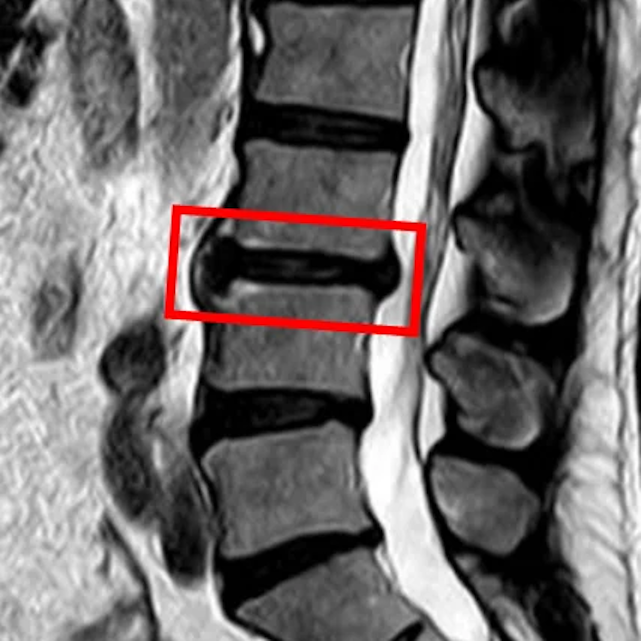

По данным МРТ и результатам осмотра пациента выявлена межпозвоночная грыжа диска L3/L4.

Симптомы по 10-балльной шкале (0 – отсутствие симптомов, 10 – сильные боли/онемение):

– боли в пояснице: 10;

– боли в ногах: 0;

– онемение в ногах: 0;

– боли в ягодицах: 0.